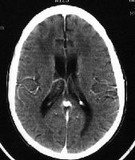

• Aids dementia complex на CT слици као један од симптома полно преносиве болести СИДЕ чије преношење може бити и оралним путем